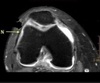

INFRASPINATUS MUSCLE

How well did you know this?

1

Not at all

2

3

4

5

Perfectly

10

Q

What is letter D?

A

GLENOID